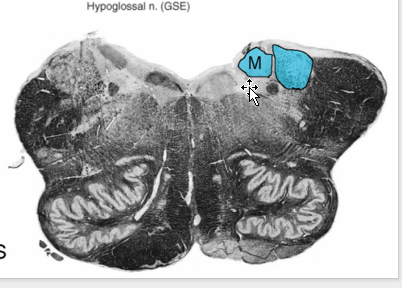

Hypoglossal Nucleus:

Location:

deep to hypoglossal trigone

either side of median sulcus in medullary portion of rhomboid fossa

Function:

(GSE) to most of tongue (except palatoglossus; CN X)

Route of Axons (motor neurons):

travel ventrally lateral to medial lemniscus → brainstem in preolivary sulcus.

Cortical innervation

bilateral w/ contralateral preponderance (more contribution from contra side)

Ipsilateral input allows for functional recovery in the case of a supranuclear lesion.